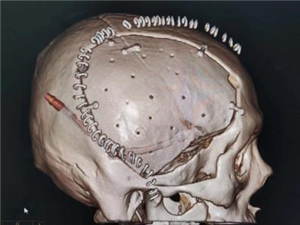

病例 3:60 岁男性开颅术后颅骨缺损,选择 PEEK(聚醚醚酮)材料进行修补。

术前:

术后: